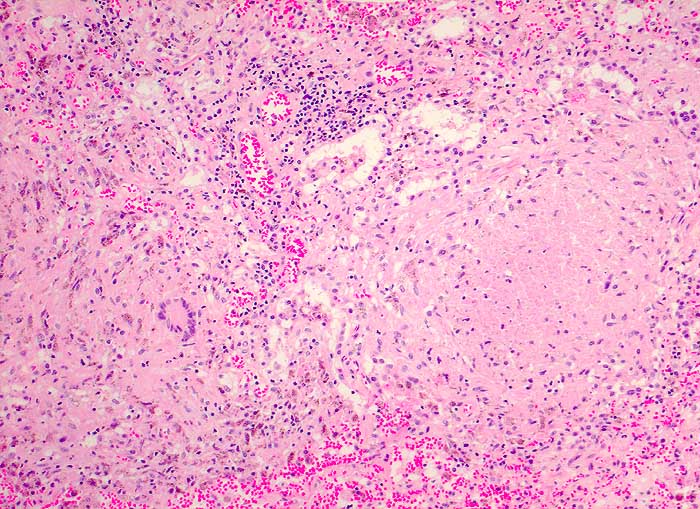

Verkäsende Granulome mit Langhansriesenzellen.

Autopsiebefunde: Miliare Streuherde in Lunge, Milz (Dm bis 4mm), Nieren, Nebennieren, Ileum terminale und Zoekum (Tuberkulosepsis) mit Nachweis säurefester Stäbchen. Lymphknotentuberkulose zervikal beidseits (Dm bis 2x1cm), peribronchial beidseits, paraaortal abdominal (vor allem peripankreatisch), mesenterial und ileozökal (Dm bis 2x2cm). Nachweis von Mycobacterium tuberculosis in Abstrich von Milz und Lunge sowie in der broncho-alveolären Lavage 2 Wochen vor dem Tod. Käsige Pneumonie beider Lungen. Fibrinöse Pleuritis beidseits.

Generalisierte Lymphadenopathie, Stomatitis, HIV positiv.

Während bei immunkompetenten Patienten der Halslymphknotenbefall meist auf einen Primärinfekt im Bereich der Mundhöhle (Typ Bovinus) hindeutet, sind bei HIV Patienten die Lymphknoten wahrscheinlich im Rahmen einer generalisierten hämatogenen und lymphogenen Tuberkulose befallen (Miliartuberkulose).